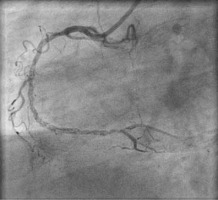

Dissection after predilatation, before BVS implantation, occurred in 22 patients, and in 17 of them it was covered by BVS implantation with optimal angiographic results. Five of them were finally in the dissection group. In another 4 patients from the dissection group, dissection appeared after BVS implantation and required additional intervention, but it was absent after predilatation. The description of dissection according to the NHLBI classification [2] is presented in Table I. Examples of angiographic images of individual dissection classes are shown in Table II.

Table II

Coronary artery dissection – classification